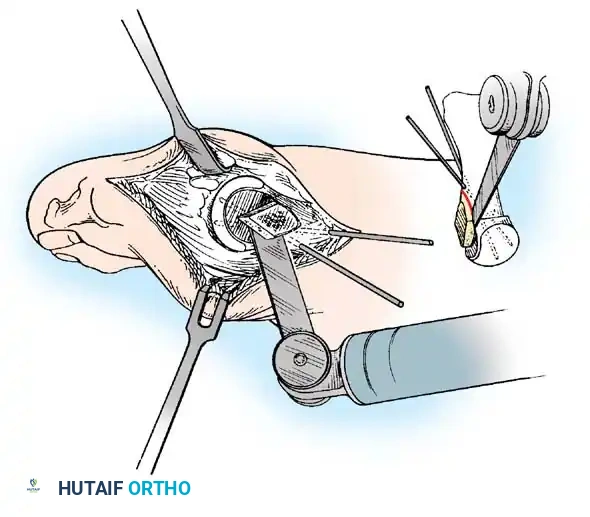

The following modifi cations of the Keller technique can expand the indications for use with more severe deformities.

REMOVAL OF THE FIBULAR SESAMOID

• When the medial eminence and phalangeal base have been excised, remove the fi bular sesamoid.

• Place a sturdy two-toothed retractor beneath the metatarsal head, and have an assistant lift it dorsally.

• Using a Freer elevator or a small osteotome for its strength, mobilize the fi bular sesamoid (Fig. 78-31A to C). This may be diffi cult in elderly patients with signifi cant deformity and adherence of the sesamoid to the metatarsal head. Lift the metatarsal dorsally for exposure (Fig. 78-31D and E).

• When the sesamoid is mobile, identify the fl exor hallucis longus tendon by placing traction on the hallux and fl exing and extending the interphalangeal joint of the hallux. The tendon is visible just distal to and in alignment with the sesamoids, which straddle it.

• Identify and expose the lateral neurovascular bundle just lateral to the tendon by blunt dissection.

• Pull the plantar medial capsule medially. This requires a fi rm grasp on the capsule. The medial traction brings the intersesamoid “ligament” into better view.

• Incise the intersesamoid ligament longitudinally with a No. 67 Beaver or No. 15 Bard-Parker blade. If tenotomy scissors are used, place one arm of the scissors under the ligament (this arm rests on the dorsal side of the fl exor hallucis longus) and the other arm dorsal to the ligament.

• When the intersesamoid ligament is incised, grasp the sesamoid fi rmly with forceps or a small Kocher clamp, fl ex the toe at the interphalangeal and metatarsophalangeal joints to relax the fl exor hallucis longus tendon, and pull the fi bular sesamoid distally and medially.

• With release of the intersesamoid ligament, the medial surface of the fi bular sesamoid is free from soft tissue. Distally, the sesamoid is free because of resection of the base of the proximal phalanx. This leaves two sides of the sesamoid, distal and medial, free of soft tissue.

• While pulling the sesamoid distally and medially, use a small blade to incise along the lateral margin of the sesamoid under direct vision. Keep pulling the head of the metatarsal dorsally and holding the hallux distracted and in fl exion. This greatly aids in identifi cation of the margins of the fi bular sesamoid, particularly laterally and proximally.

• The most diffi cult part of the sesamoidectomy and that which should be done last is release of the proximal lateral corner of the sesamoid where the fl exor hallucis brevis lateral head inserts. While incising the lateral capsular attachments to the sesamoid, do not bury the blade of the knife because the neurovascular bundle to the lateral side of the hallux is just lateral to the capsule.

• Now all attachments to the fi bular sesamoid have been removed except the lateral head of the fl exor hallucis brevis, which inserts on the proximal lateral margin of the sesamoid. This is a diffi cult section to remove; however, this section can be released under direct vision by pulling the sesamoid distally and medially and lifting the metatarsal head dorsally with a strong two-toothed retractor.

• When the sesamoid has been removed, insert two 0.062-inch Kirschner wires retrograde from the tip of the toe 2 to 3 mm plantar to the nail bed, leaving about 5 to 7 mm of the pins exposed at the base of the phalangeal remnant to help align the phalanx on the metatarsal before antegrade passage of the pins into the metatarsal (Fig. 78-31F).

Fig. 78-31 Excision of fi bular sesamoid in modifi ed Keller procedure. With base of proximal phalanx removed and medial eminence excision, exposure of fi bular sesamoid is not as diffi cult from medial incision. A, Operative photograph showing elevation of fi rst metatarsal with strong two-tooth retractor and use of small osteotome to mobilize fi bular sesamoid and lateral capsuloligamentous (frequently contracted) structures. Osteotome is between metatarsal head and lateral sesamoid. When mobilization of fi bular sesamoid is complete, entire sesamoid is visible for excision. Note chondromalacia of tibial sesamoid articular surface medial to osteotome. B, Fibular sesamoid has been excised, and lateral capsular structures and conjoined tendon (in forceps) have been released. Neurovascular bundle to lateral side of hallux is adjacent to these structures. C, Diagrammatic representation of modifi ed Keller procedure. By excising fi bular sesamoid, valgus moment of conjoined tendon of fl exor hallucis brevis and adductor hallucis no longer pulls fl exor hallucis longus tendon laterally (carrying hallux with it) through capsulosesamoid plantar plate and pulley system. D, Metatarsal head must be lifted dorsally to excise fi bular sesamoid under direct vision. E, Note exposure of fi bular sesamoid after mobilization of metatarsal head. Continued